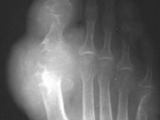

Gout-big toe

Gout-big toe